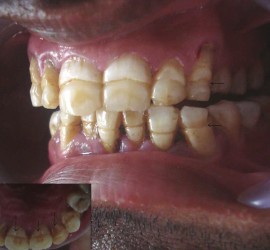

Ретроградный кариес. Кариозный процесс разрушает дентин со стороны пульпы. Наблюдается при наличии интактной, кариозной и пломбированной коронки, а также в случае гангрены пульпы кариозного и травматического происхождения. Со стороны полости пульпы идет процесс распада дентина за счет функции микроорганизмов и протеолитических ферментов. Ретроградный кариес может иметь место при хроническом пролиферативном […]